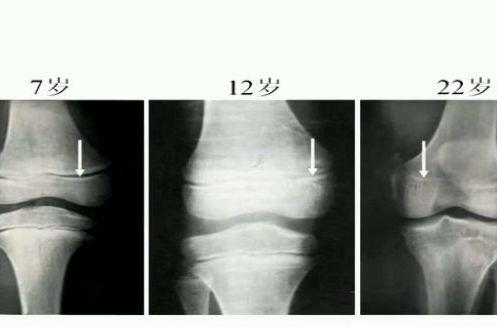

腿部拉伸成长——骨骺

人体中有些软骨终身都不会骨化的,例如:喉、咽、鼻子、耳朵都是由软骨组成的。在我们生长发育过程中,软骨会慢慢的长成骨头, 骨骺就是骨头成长时末端的软骨。当骨骺的软骨完全骨化后骨骺线闭合,骨骼既随之停止生长。